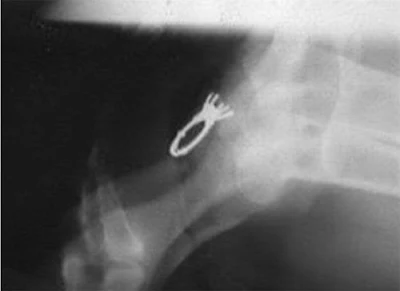

Benda Benda Asing di Dalam Perut Anjing

Mata Kail